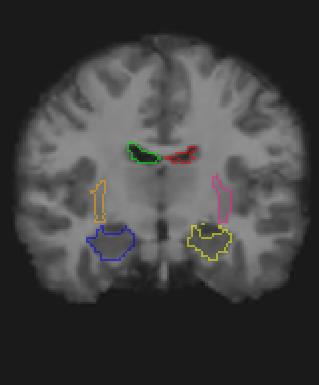

Medical image registration is a fundamental and critical task in medical image analysis. With the rapid development of deep learning, convolutional neural networks (CNN) have dominated the medical image registration field. Due to the disadvantage of the local receptive field of CNN, some recent registration methods have focused on using transformers for non-local registration. However, the standard Transformer has a vast number of parameters and high computational complexity, which causes Transformer can only be applied at the bottom of the registration models. As a result, only coarse information is available at the lowest resolution, limiting the contribution of Transformer in their models. To address these challenges, we propose a convolution-based efficient multi-head self-attention (CEMSA) block, which reduces the parameters of the traditional Transformer and captures local spatial context information for reducing semantic ambiguity in the attention mechanism. Based on the proposed CEMSA, we present a novel Symmetric Transformer-based model (SymTrans). SymTrans employs the Transformer blocks in the encoder and the decoder respectively to model the long-range spatial cross-image relevance. We apply SymTrans to the displacement field and diffeomorphic registration. Experimental results show that our proposed method achieves state-of-the-art performance in image registration. Our code is publicly available at \url{https://github.com/MingR-Ma/SymTrans}.